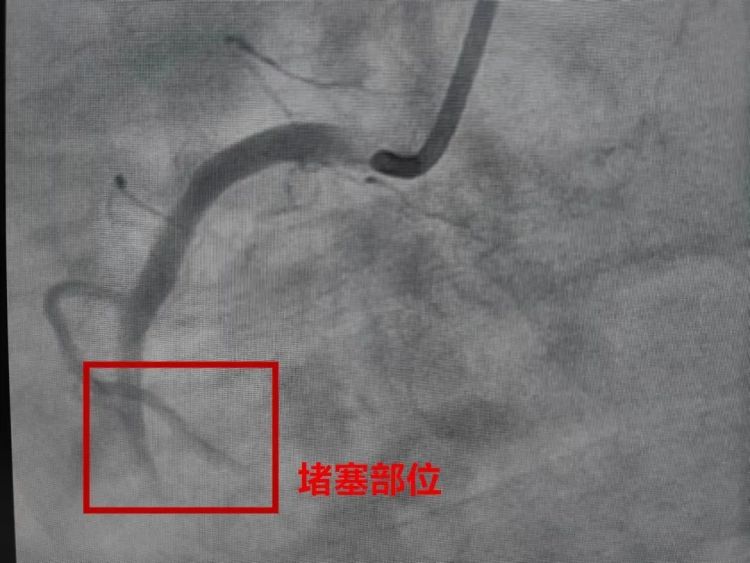

心梗即“心肌梗死”

是心脏的危急重症之一

它是由于冠状动脉发生堵塞

出现急性、持续性的缺血缺氧

从而引起的心肌坏死